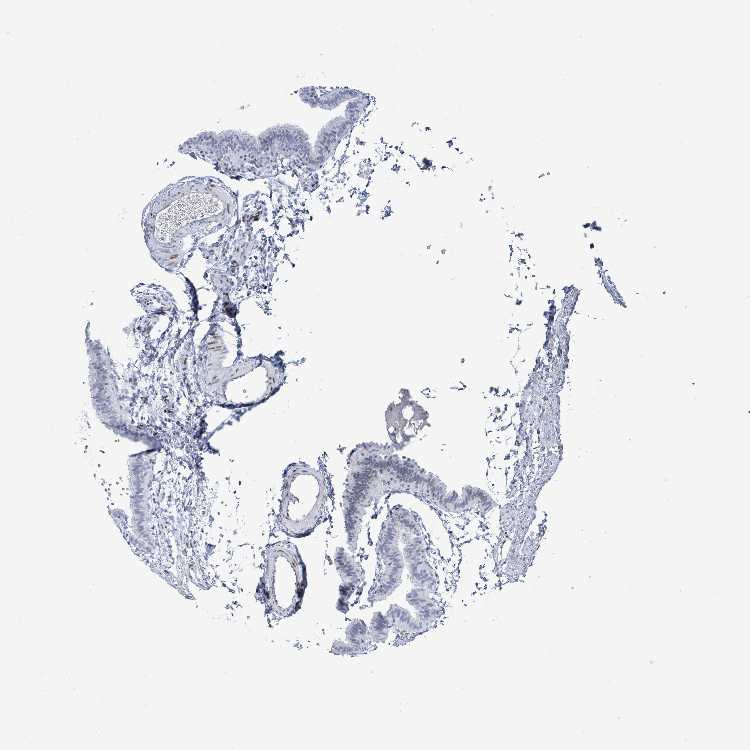

TISSUE PRIMARY DATA FALLOPIAN TUBE Show tissue menu

FALLOPIAN TUBE - Antibody stainingi

Antibody staining in the annotated cell types in the current human tissue is reported as not detected, low, medium, or high, based on conventional immunohistochemistry profiling in selected tissues. This score is based on the combination of the staining intensity and fraction of stained cells.

Each image is clickable and will lead to virtual microscopy that enables deeper exploration of all samples and also displays staining intensity scores, fraction scores and subcellular localization as well as patient and tissue information for each sample.

Antibody HPA051410

Glandular cells Not detected